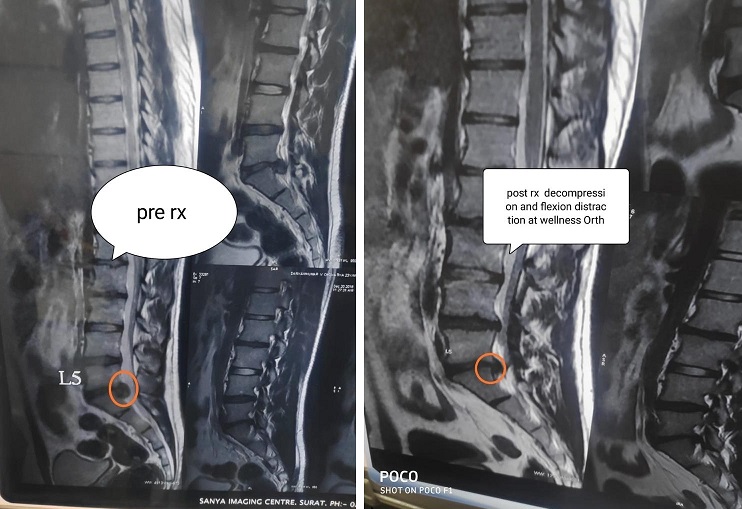

Decompression & Flexion Distraction

4: Decompression & Flexion Distraction